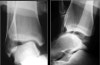

영상 검사

발목관절이나 거골하 관절의 불안정이 의심되면 varus & anterior stress x-ray 검사를 하고 반대편 발에서도 검사를 하여 비교하도록 합니다.

X-ray : Lateral ankle instability